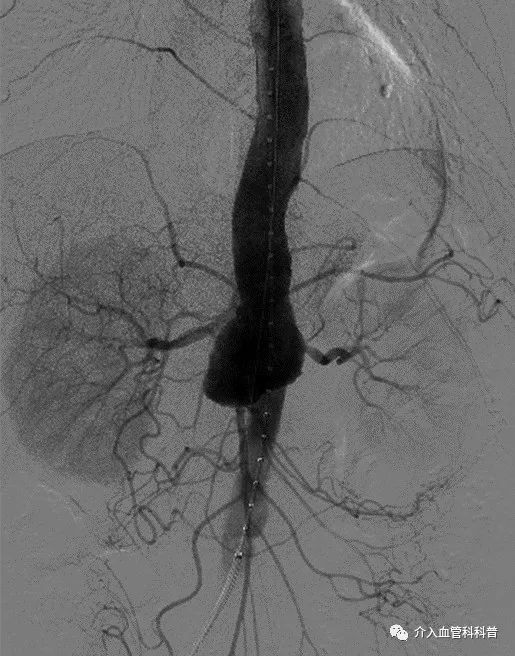

胸腹主动脉瘤术前CTA

患者是一名70岁的男性,因腹部及腰背部疼痛1周行CT检查发现胸腹主动脉瘤。瘤体最大径6cm,累及双肾动脉,常规腹主动脉腔内修复手术无法治疗,遂转至南昌大学第二附属医院治疗。

术后造影显示,患者胸腹主动脉瘤修复良好,无内漏,各内脏分支动脉血流灌注良好,术后患者康复出院。